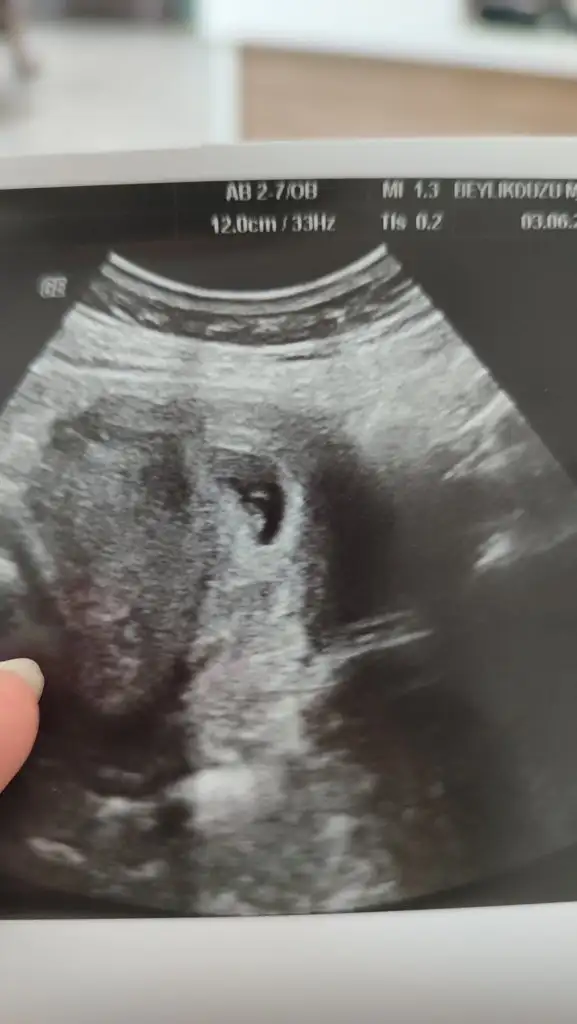

Hülya hanım 8 haftalık görüntü karından yorumlar mısınız lütfen6-7-8 haftalik baska usg var mi

Merhaba 8 haftalık karından yorumlar musun lütfenMerhaba Allah kucağınıza almayı nasip etsinerkek bence